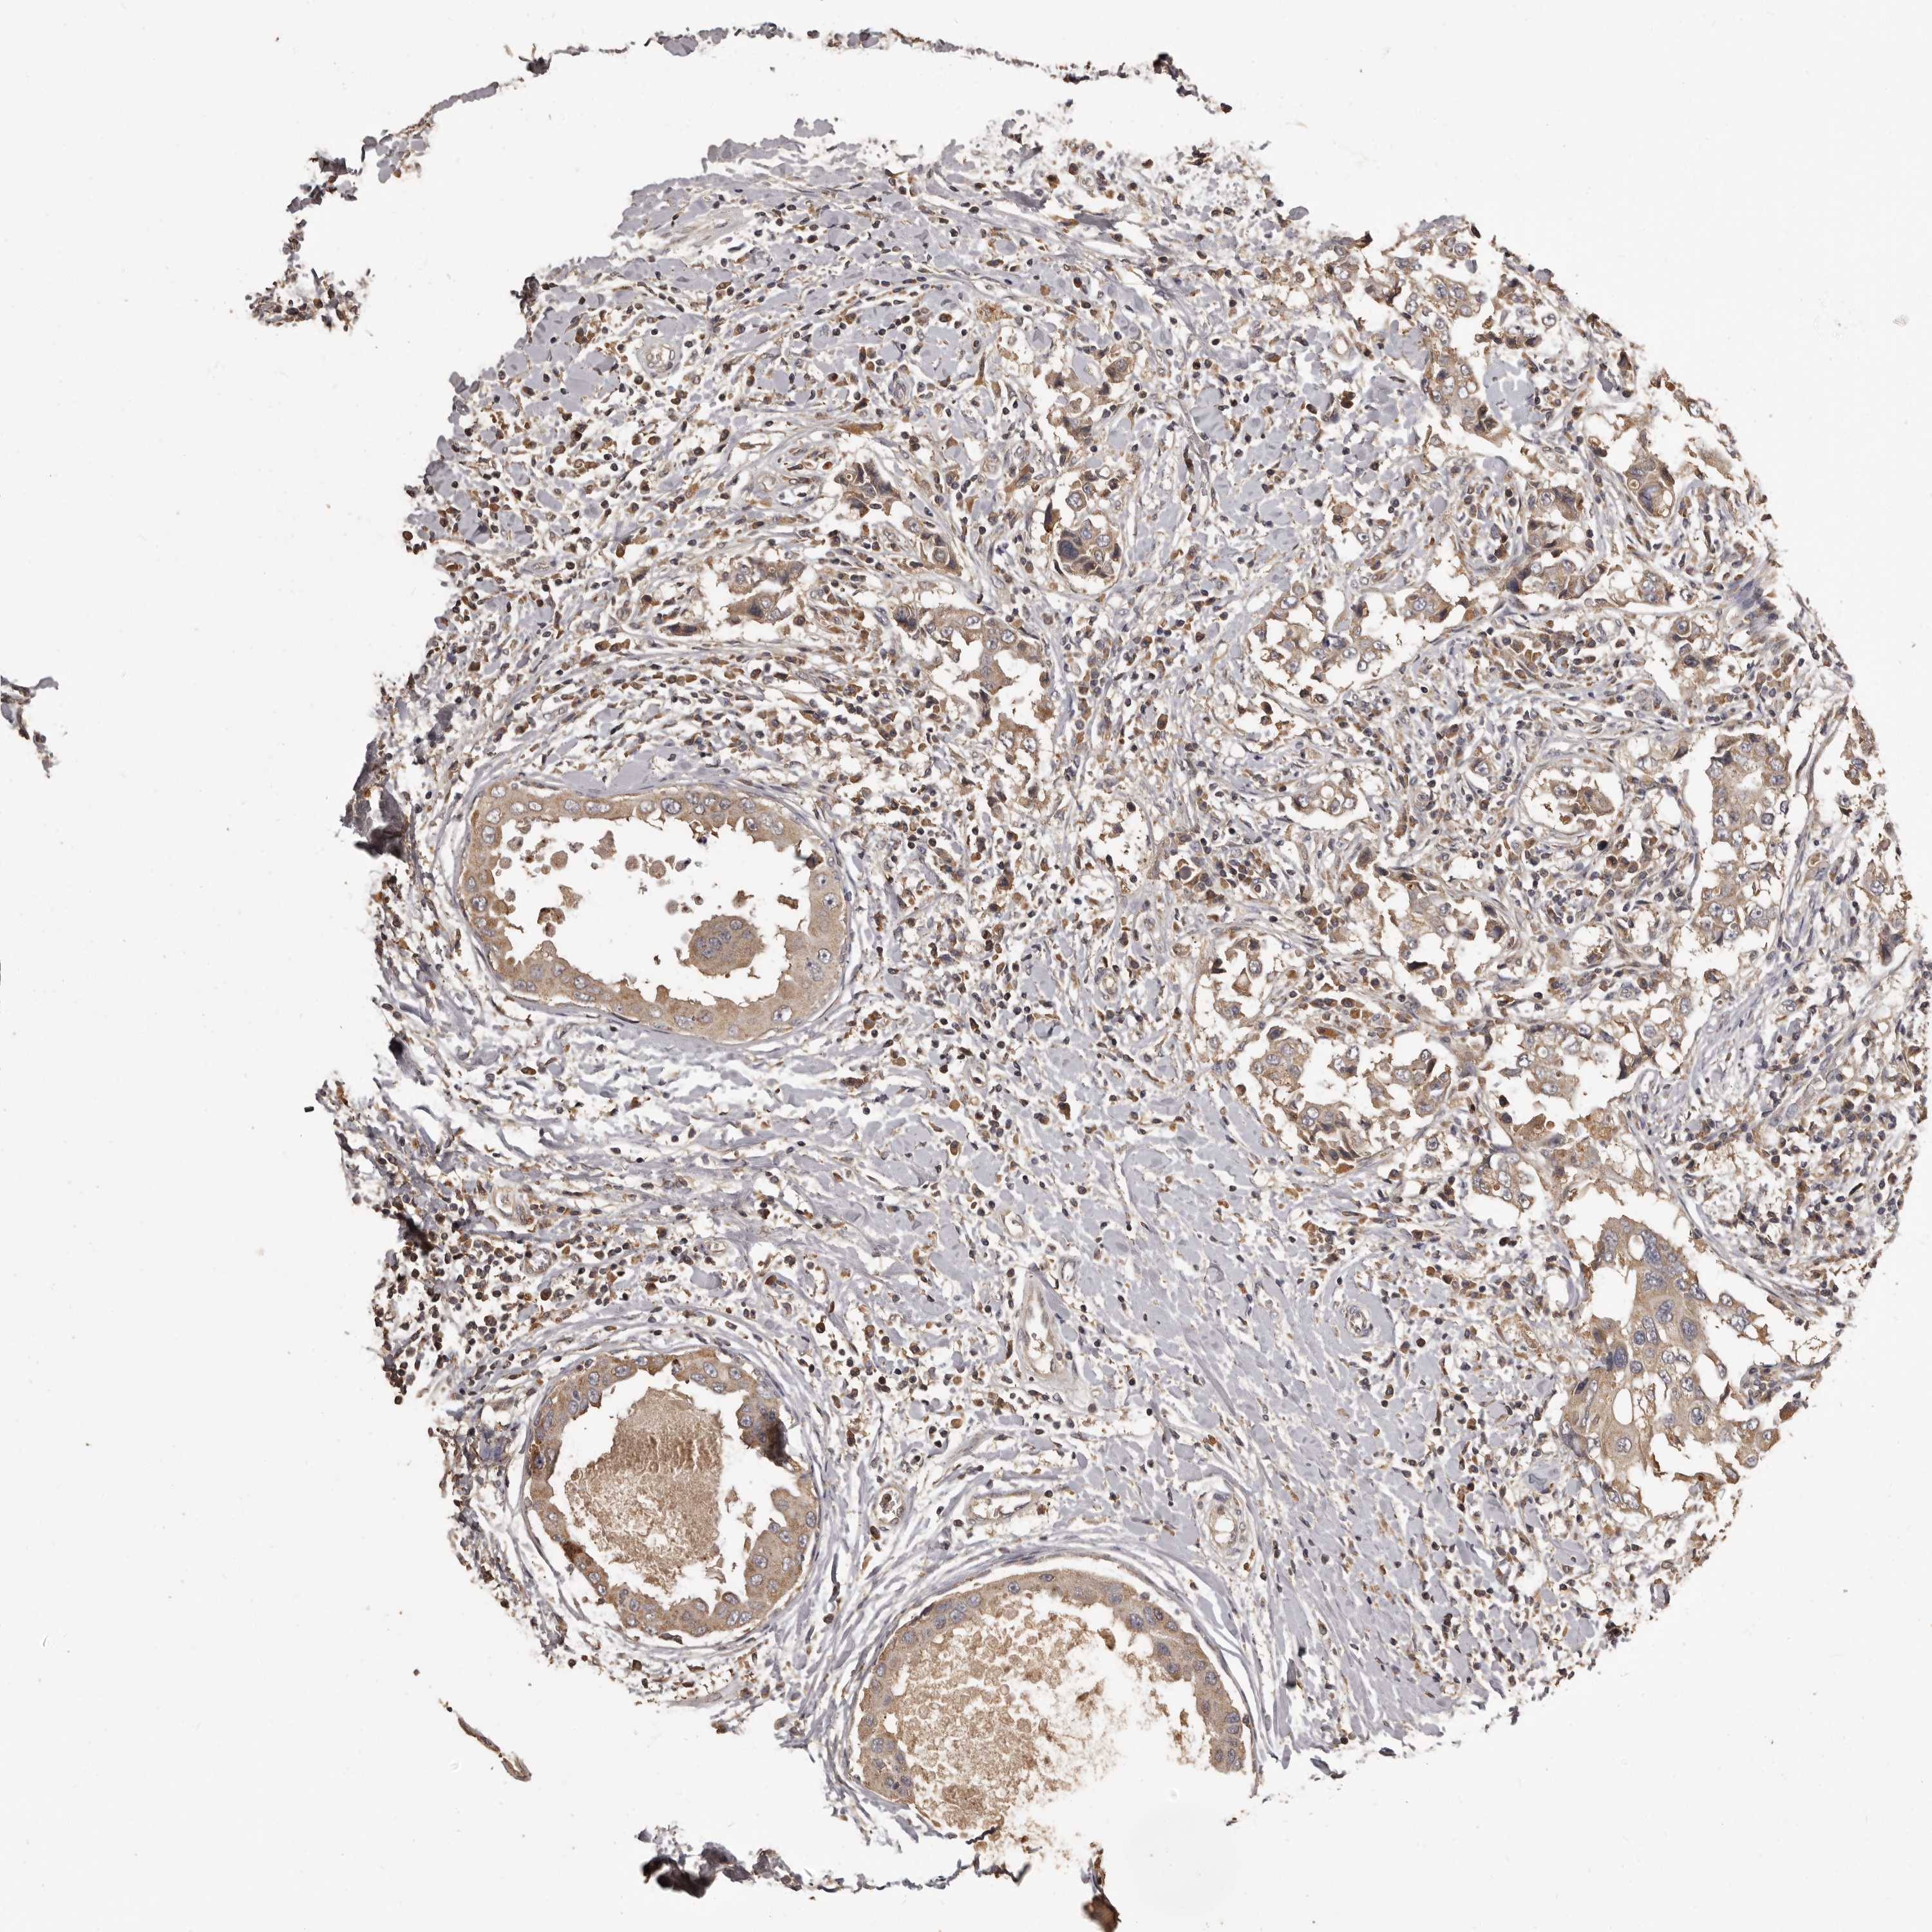

CANCER BREAST CANCER Show tissue menu

BRCA TCGA BRCA VALIDATION PROTEIN EXPRESSION

ANTIBODIES

AND

VALIDATION